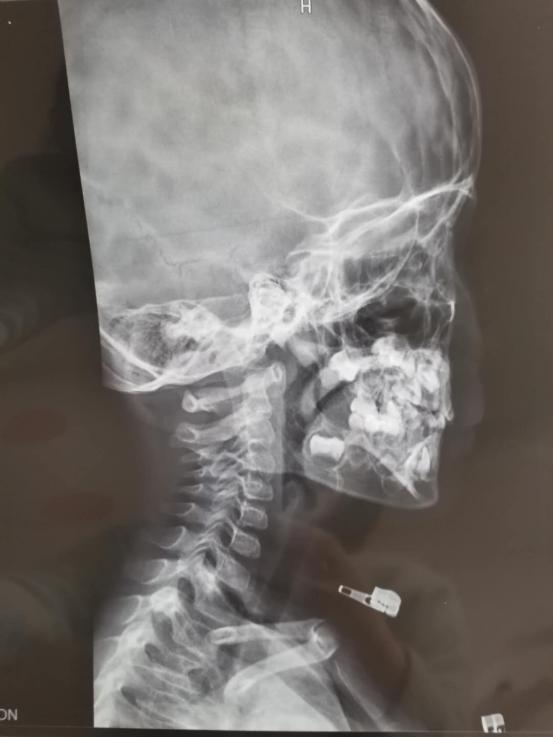

有口臭,不咳嗽,但是晚上睡觉时流口水,感觉有时候会被口水呛到,时不时咳嗽一下。嗓子总是红色的,扁桃体发过一次炎,现在不到二度,腺样体从去年12月份张口呼吸,又憋气,以前就是睡觉呼吸声音有点粗,没有打呼噜,现在大约睡半个小时就有憋气现象。

现在的主要症状有这4点:1.腺样体肥大,睡觉有憋气;2.青蛙肚,吃完饭后,肚子大,用手一敲,咚咚的;3、孩子的小鸡鸡有几天晚上老是痒,用盐水洗了以后才缓解;4、运动后出汗特别多,比别人爱出汗。最迫切的是希望能解决孩子睡觉憋气问题,和孩子的肠漏问题。

小患者的辅助检查做了鼻咽喉镜、食物肠道过敏检查、肠道通透性评估。小患者存在腺样体肥大,鸡蛋III度慢敏,燕麦、红辣椒II度,牛奶、西红柿、巧克力、牡蛎I度;甘露醇回收比率过高。于是首先让孩子家长对小患者进行食物轮替和肠道修复,同时注意健脾消食。

经一段时间治疗后,患儿大便有所好转,现大便1-2日一行,排便较前轻松,但仍有鼻塞憋气,睡觉打呼、张口呼吸、食欲亢进,多食易饥,易积食口臭,身材偏矮小瘦弱,肌肉松软,不喜运动,脾气急躁,专注力差小便少,色黄等症状。